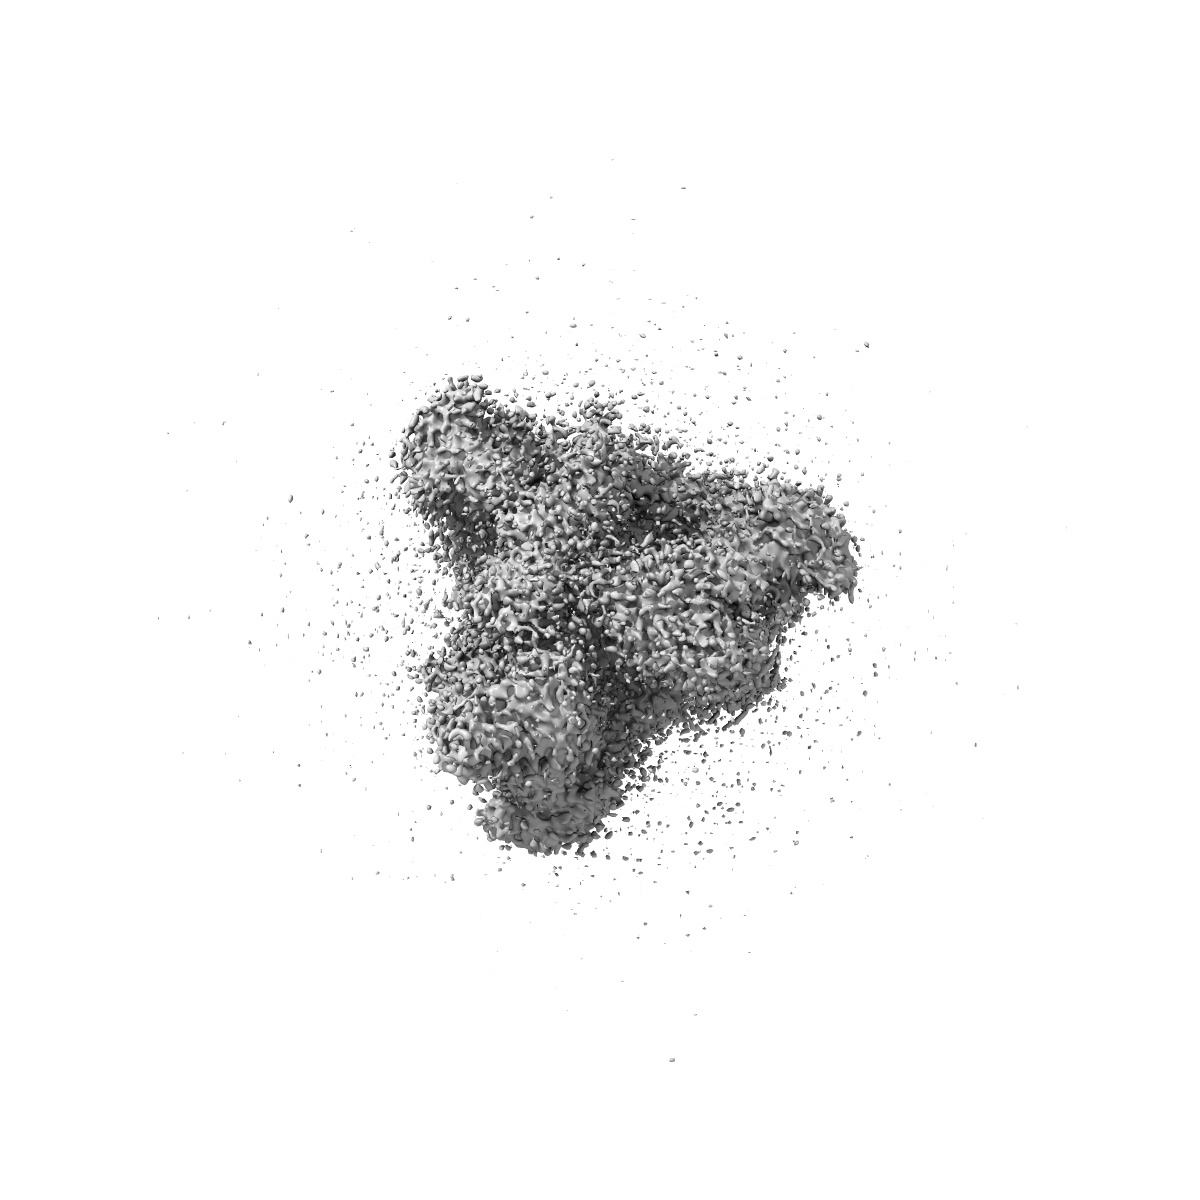

SARS-CoV-2 Spike protein in complex with the single chain fragment scFv76

Single-particle3.5 Å

Sample: SARS-CoV-2 Spike protein in complex with the single chain fragment scFv76